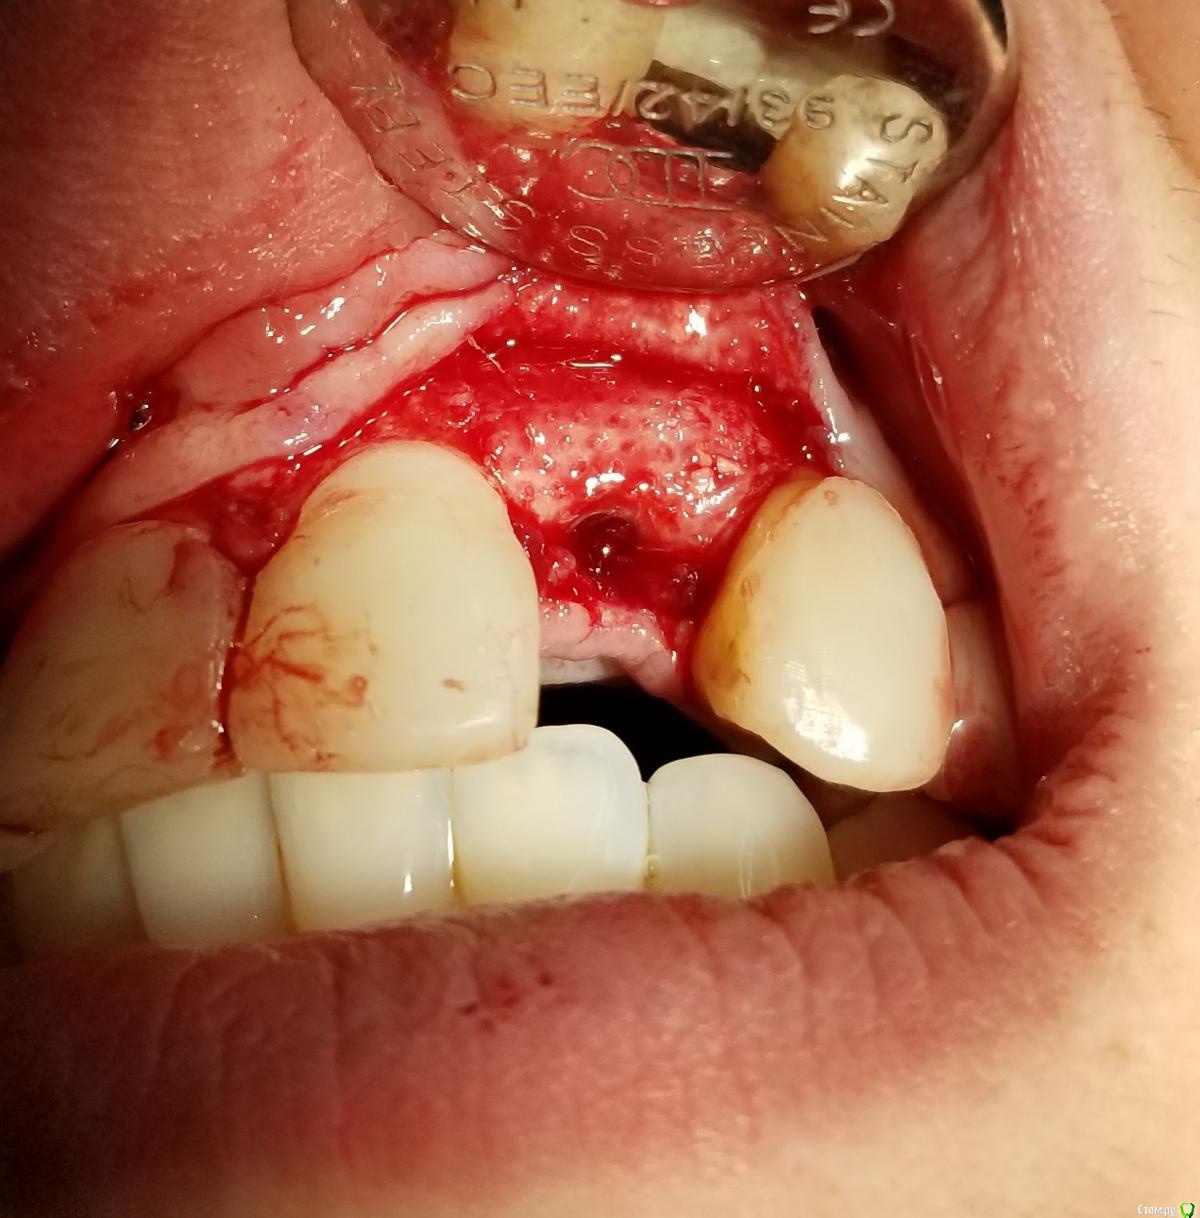

Kostoprav Опубликовано 19 сентября, 2018 Автор Поделиться Опубликовано 19 сентября, 2018 (изменено) сегодня установил фдм, десна и вправду на центральном немного задралась, уложил 2 сочных сст под лоскут. Больше разрез через зенит делать не буду. Спасибо всем за советы! Изменено 19 сентября, 2018 пользователем Kostoprav Ссылка на комментарий

an_ver Опубликовано 29 сентября, 2018 Поделиться Опубликовано 29 сентября, 2018 У шейки недопаковано было, апикальной лучше фиксировать, вертикальные разрезы надо не так делать. Спейсер неродной что ли?При таком виде верт.разрезов практически всегда ресессия обеспечена Ссылка на комментарий